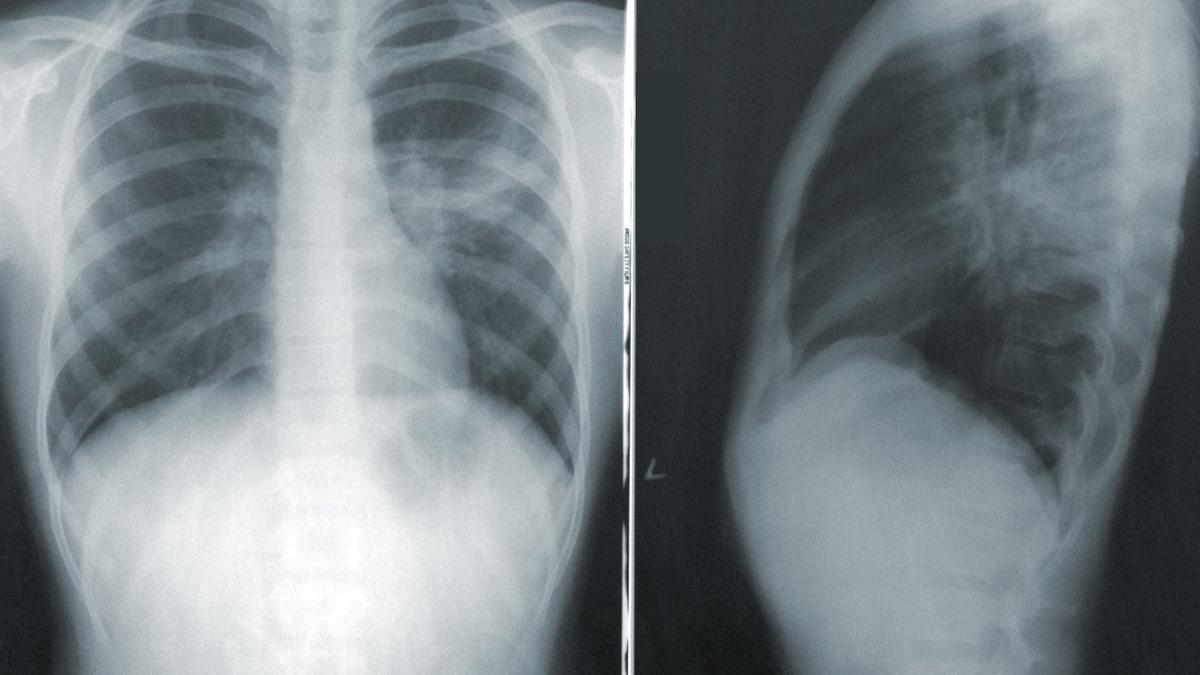

Глухой кашель Ковидом в 2021 году могли переболеть 18 млн россиян — это вдвое больше, чем согласно официальной статистике. Посмотрите на этот график